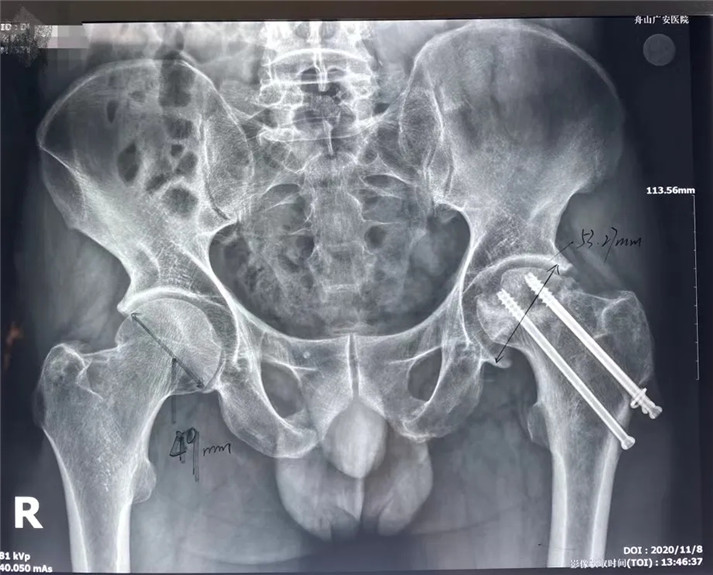

結(jié)合影像學(xué)表現(xiàn)研究后,骨科中心羅軍主任診斷丁先生為左股骨頭壞死,并建議其行全髖關(guān)節(jié)置換手術(shù)。

術(shù)前

考慮到患者的年齡、骨折類型等情況,以及患者的種種擔(dān)憂,為精準(zhǔn)治療、加快愈合、避免關(guān)節(jié)脫位及肢體長短不等,羅軍主任團隊采用了近期引進的AI HIP置換術(shù)前規(guī)劃系統(tǒng)為患者行術(shù)前規(guī)劃。他們將丁先生的術(shù)前CT數(shù)據(jù)導(dǎo)入到系統(tǒng)中,通過自動識別骨盆和股骨建立了計算機數(shù)字三維模型。AI HIP顯示患者適合使用合適的髖臼杯、股骨柄、標(biāo)準(zhǔn)陶瓷球頭、陶瓷內(nèi)襯,并精準(zhǔn)定位了截骨線,可以有效幫助醫(yī)生在手術(shù)中做到精確截骨。